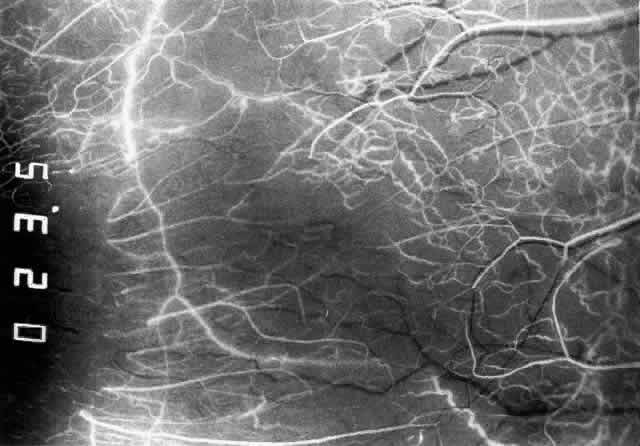

The characteristic features of necrotizing scleritis on fluorescein angiography are hypoperfusion and, eventually, nonperfusion of the vascular networks (Figs. 40 through 43).26 The initial changes are on the venous side of the capillary network; the transit time of the dye increases even if the eye is red and congested. If the disease process persists or has been present for a long time, thrombosis and permanent vaso-occlusive changes occur. These vessels (or the occluded capillary network) are bypassed by the opening of anastomotic channels. New vessels in a granuloma give rise to deep intrascleral leakage of dye (see Fig. 43). Conjunctival and episcleral involvement by the destructive change is late but is always preceded by vaso-occlusive changes that can sometimes be detected with use of the red-free light on the slit lamp (Figs. 44 and 45).

Fig. 40. Early necrotizing scleritis. There is characteristic yellow discoloration of the sclera underlying the conjunctiva at a point of necrosis. In this instance a small filament of tissue has penetrated the conjunctiva.

Fig. 41. Late stage of fluorescein angiogram adjacent to the site of necrosis in the same patient as in Figure 40. Although the eye is uniformly congested, the area near the necrosis shows vascular shutdown, whereas the rest of the conjunctiva and episclera is normally perfused.

Fig. 42. Late arterial phase of fluorescein angiogram in a patient with necrotizing scleritis. All the vessels except the main trunk and the vessels around the limbal perforating vessels are occluded and remain unperfused throughout the angiogram.

Fig. 43. Late venous phase of angiogram of a patient with necrotizing scleritis showing late deep leakage from vessels on the surface of the sclera and leakage of the capillary network at the limbus and the vessels draining it, together with poor or absent perfusion of the remaining vessels.